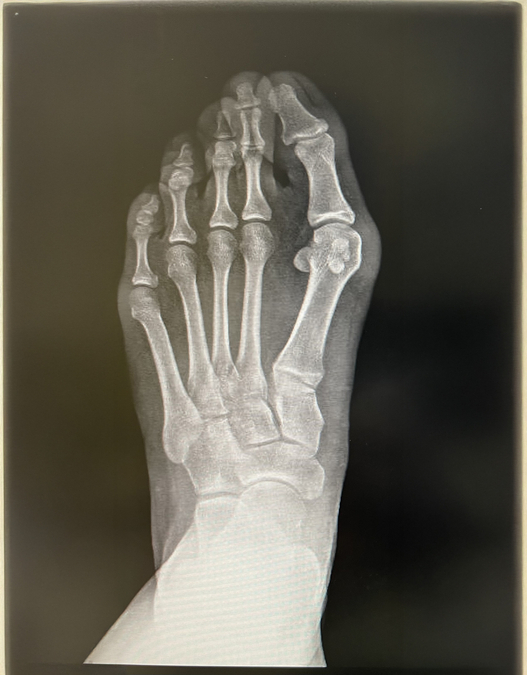

All bunion cases are best assessed by an orthopaedic consultant who specialises in foot and ankle conditions. Their treatment plan is often formed by using images such as X-rays or sometimes an MRI scan. At HCA UK we can offer a variety of treatments, including conservative options which don’t involve surgery, depending on the pain level and how your foot looks. Having an expert discuss your options with you can be very helpful.

x-ray 1.jpg x-ray 2.jpg

Bunions are swellings of the big toe joint. They’re often painful because of footwear rubbing, but there is a risk of deeper pain developing over time if the bunions aren't treated. Bunions can also cause pain when they rub onto the second toe and can, in some cases, even cause the second toe to dislocate.